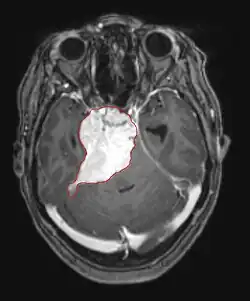

Hersenmetastasen zijn de meest voorkomende intracraniële neoplasmata bij volwassenen en komen tien keer vaker voor dan primaire hersentumoren. Ze stappen op 20 tot 40 procent van de volwassenen met kanker en worden voornamelijk geassocieerd met long- en borstkanker en melanoom. Deze laesies zijn het gevolg van de verspreiding van kankercellen door de bloedbaan en komen meestal voor op de kruising van grijze en witte stof, waar de dwarsdoorsnede van bloedvaten verandert, waardoor tumorcelembolie wordt opgesloten . 80 procent van de laesies komt voor in de hersenhelften, procent in het cerebellum en 5 procent in de hersenstam. Ongeveer 80 procent van de patiënten heeft een voorgeschiedenis van systemische kanker en 70 procent heeft meerdere hersenmetastasen.

Hersenmetastasen zijn de meest voorkomende intracraniële neoplasmata bij volwassenen en komen tien keer vaker voor dan primaire hersentumoren. Ze stappen op 20 tot 40 procent van de volwassenen met kanker en worden voornamelijk geassocieerd met long-en borstkanker en melanoom. Deze laesies zijn het gevolg van de verspreiding van kankercellen door de bloedbaan en komen meestal voor op de kruising van grijze en witte stof, waar de dwarsdoorsnede van bloedvaten verandert, waardoor tumorcelembolie wordt opgesloten. 80 procent van de laesies komt voor in de hersenhelften, procent in het cerebellum en 5 procent in de hersenstam. Ongeveer 80 procent van de patiënten heeft een voorgeschiedenis van systemische kanker en 70 procent heeft meerdere hersenmetastasen.

De literatuur laat gelijkwaardige resultaten zien voor chirurgie en radiochirurgie. Dit laatste lijkt handiger, effectiever en veiliger voor kleine laesies of in gebieden die niet toegankelijk zijn voor chirurgie. Radiochirurgie is een verstandig alternatief voor patiënten die om medische redenen niet geopereerd kunnen worden. Chirurgie is echter duidelijk de optimale methode om weefsels te verkrijgen voor diagnose en om de laesies te verwijderen die een massa-effect veroorzaken. Daarom moeten radiochirurgie en chirurgie beter worden beschouwd als twee complementaire maar verschillende methoden die moeten worden toegepast, afhankelijk van de verschillende situatie van de patiënt. Voor bijna 50 procent van de patiënten met een of twee hersenmetastasen komt niet in aanmerking voor chirurgische verwijdering vanwege de ontoegankelijkheid van de laesies, de omvang van de systemische ziekte of andere factoren. Deze en andere patiënten met meerdere metastasen krijgen gewoonlijk panencefale bestralingstherapie als standaardbehandeling. Bereik eigenlijk tot bijna 50 procent van hen met deze therapie een verbetering van neurologische symptomen en 50 tot 70 procent een merkbare reactie. Chemotherapie wordt zelden primair gebruikt voor hersenmetastasen.

Voor de meeste patiënten met hersenmetastasen is de mediane overleving slechts vier tot zes maanden na panencefale bestralingstherapie. Patiënten jonger dan 60 jaar met discrete laesies en gecontroleerde systemische ziekte kunnen echter een langere overleving bereiken omdat ze een agressievere behandelingsbenadering kunnen verdragen.